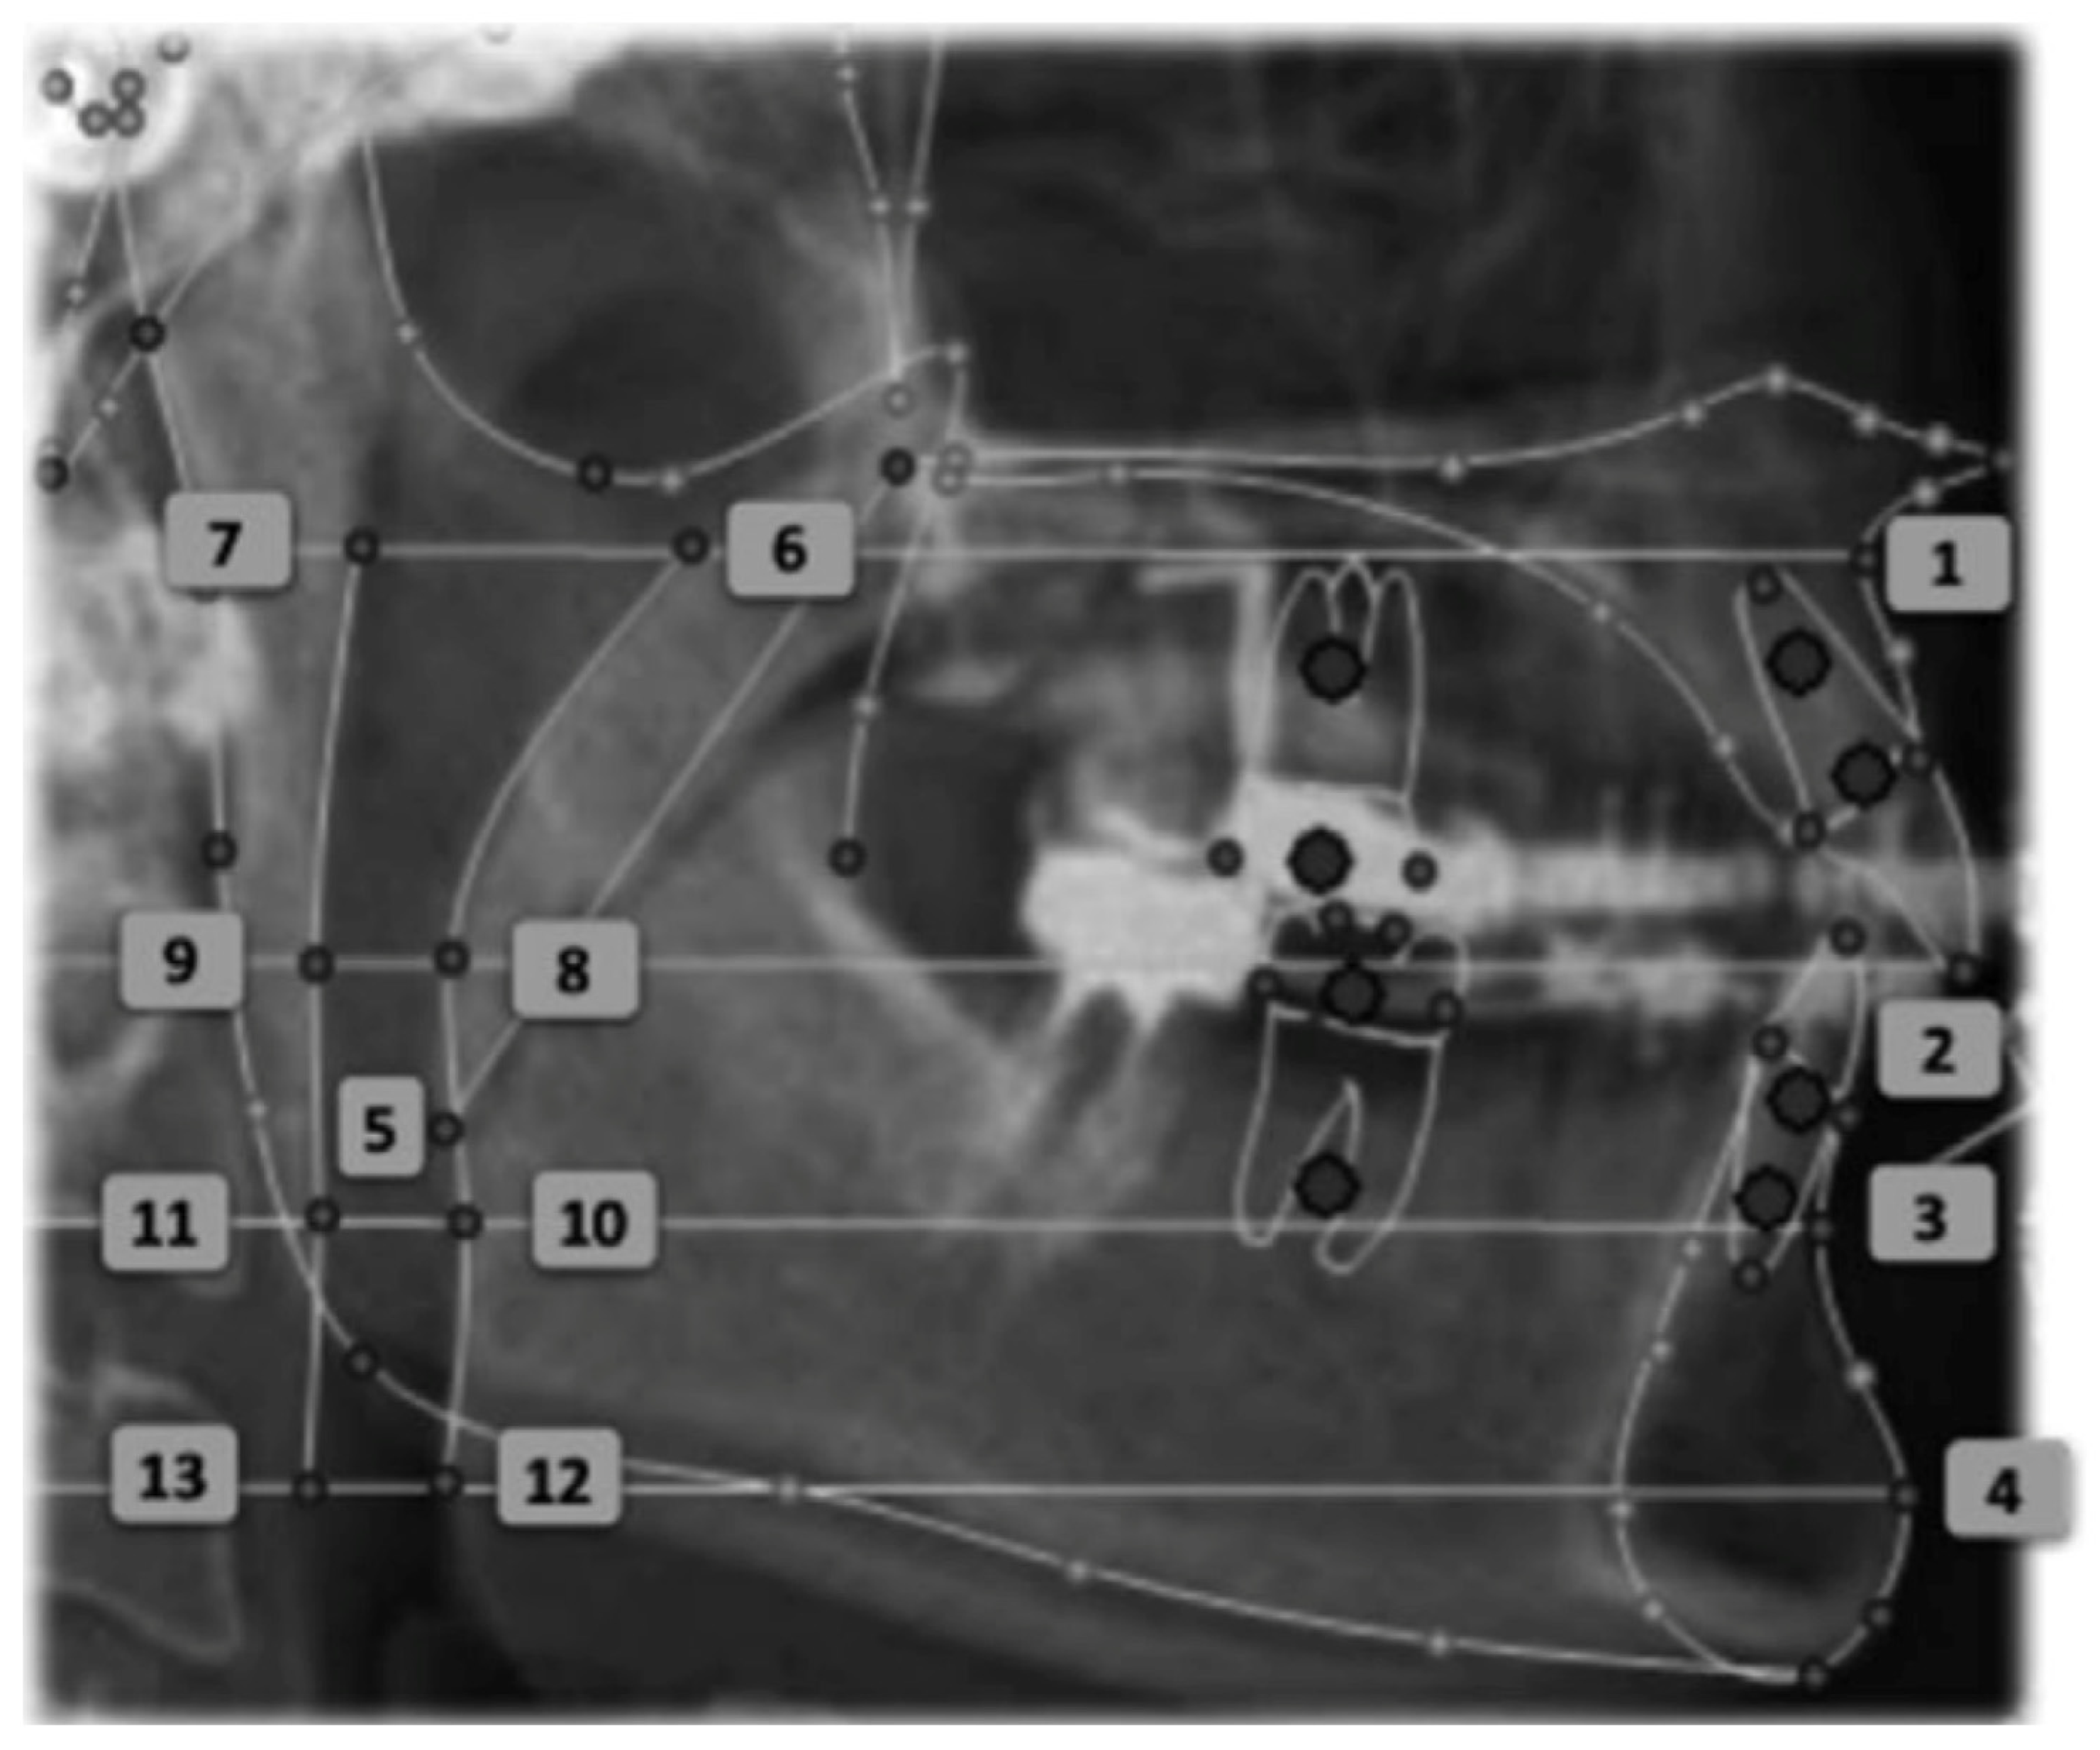

The linear measurements of the airspace proposed by the Arnett/Gunson FAB Surgery cephalometric analysis were measured at four craniometric points: A, MCI, B, Pog (Figure 3):

• SPAS at point A (SPAS at A): A line is drawn perpendicular to the true vertical line that passes through point A and extends posteriorly, intersecting the anterior (A/G anterior SPAS at A) and posterior (A/G posterior SPAS at A) limits of the superior posterior airway space. The dimension of the UA is given by the distance between these two points.

• SPAS at point MCI (SPAS at MCI): A line is drawn perpendicular to the true vertical line that passes through point MCI (point located on the incisal edge of the maxillary central incisor) and extends posteriorly, intersecting the anterior (A/G anterior SPAS at MCI) and posterior (A/G posterior SPAS at MCI) limits of the superior posterior airway (Figure 3—Points 8 and 9).

• SPAS at point B (SPAS at B): A line is drawn perpendicular to the true vertical line that passes through point B and extends posteriorly, intersecting the anterior (A/G anterior SPAS at B) and posterior (A/G posterior SPAS at B) limits of the superior posterior airway space.

• SPAS at point Pog (SPAS at Pog): A line is drawn perpendicular to the true vertical line that passes through point Pog at the anterior (A/G anterior SPAS at Pog) and posterior (A/G posterior SPAS at Pog) wall of the superior posterior airway.

Figure 3. Cephalometric points: (1) A-point, (2) MCI-point, (3) B-point, (4) Pog-point, (5) A/G tip of soft Palate, (6) A/G anterior SPAS at A, (7) A/G posterior SPAS at A, (8) A/G anterior SPAS at MCI, (9) A/G posterior SPAS at MCI, (10) A/G anterior SPAS at B, (11) A/G posterior SPAS at B, (12) A/G anterior SPAS at Pog, (13) A/G posterior SPAS at Pog.